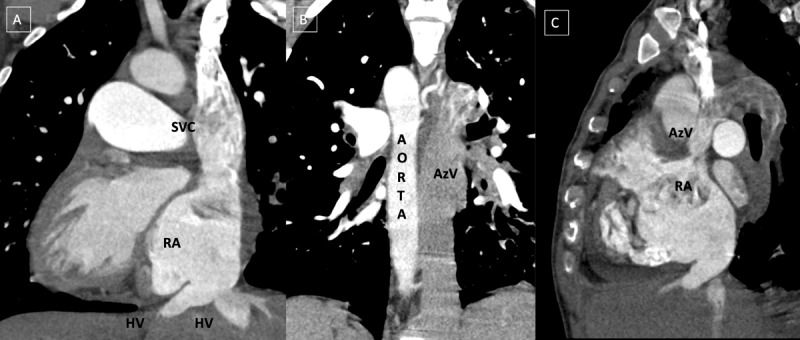

Incidental detection of polysplenia associated with situs inversus totalis in an adult is rarely reported in literature.12 "Heterotaxy" refers to a wide spectrum of anomalies involving dysmorphism of thoracoabdominal organs across the right-left axis of the body. Polysplenia is observed in left isomerism along with bilateral bilobed bronchi and bilateral morphologic left atria. However, in this case, polysplenia was present without isomerism.